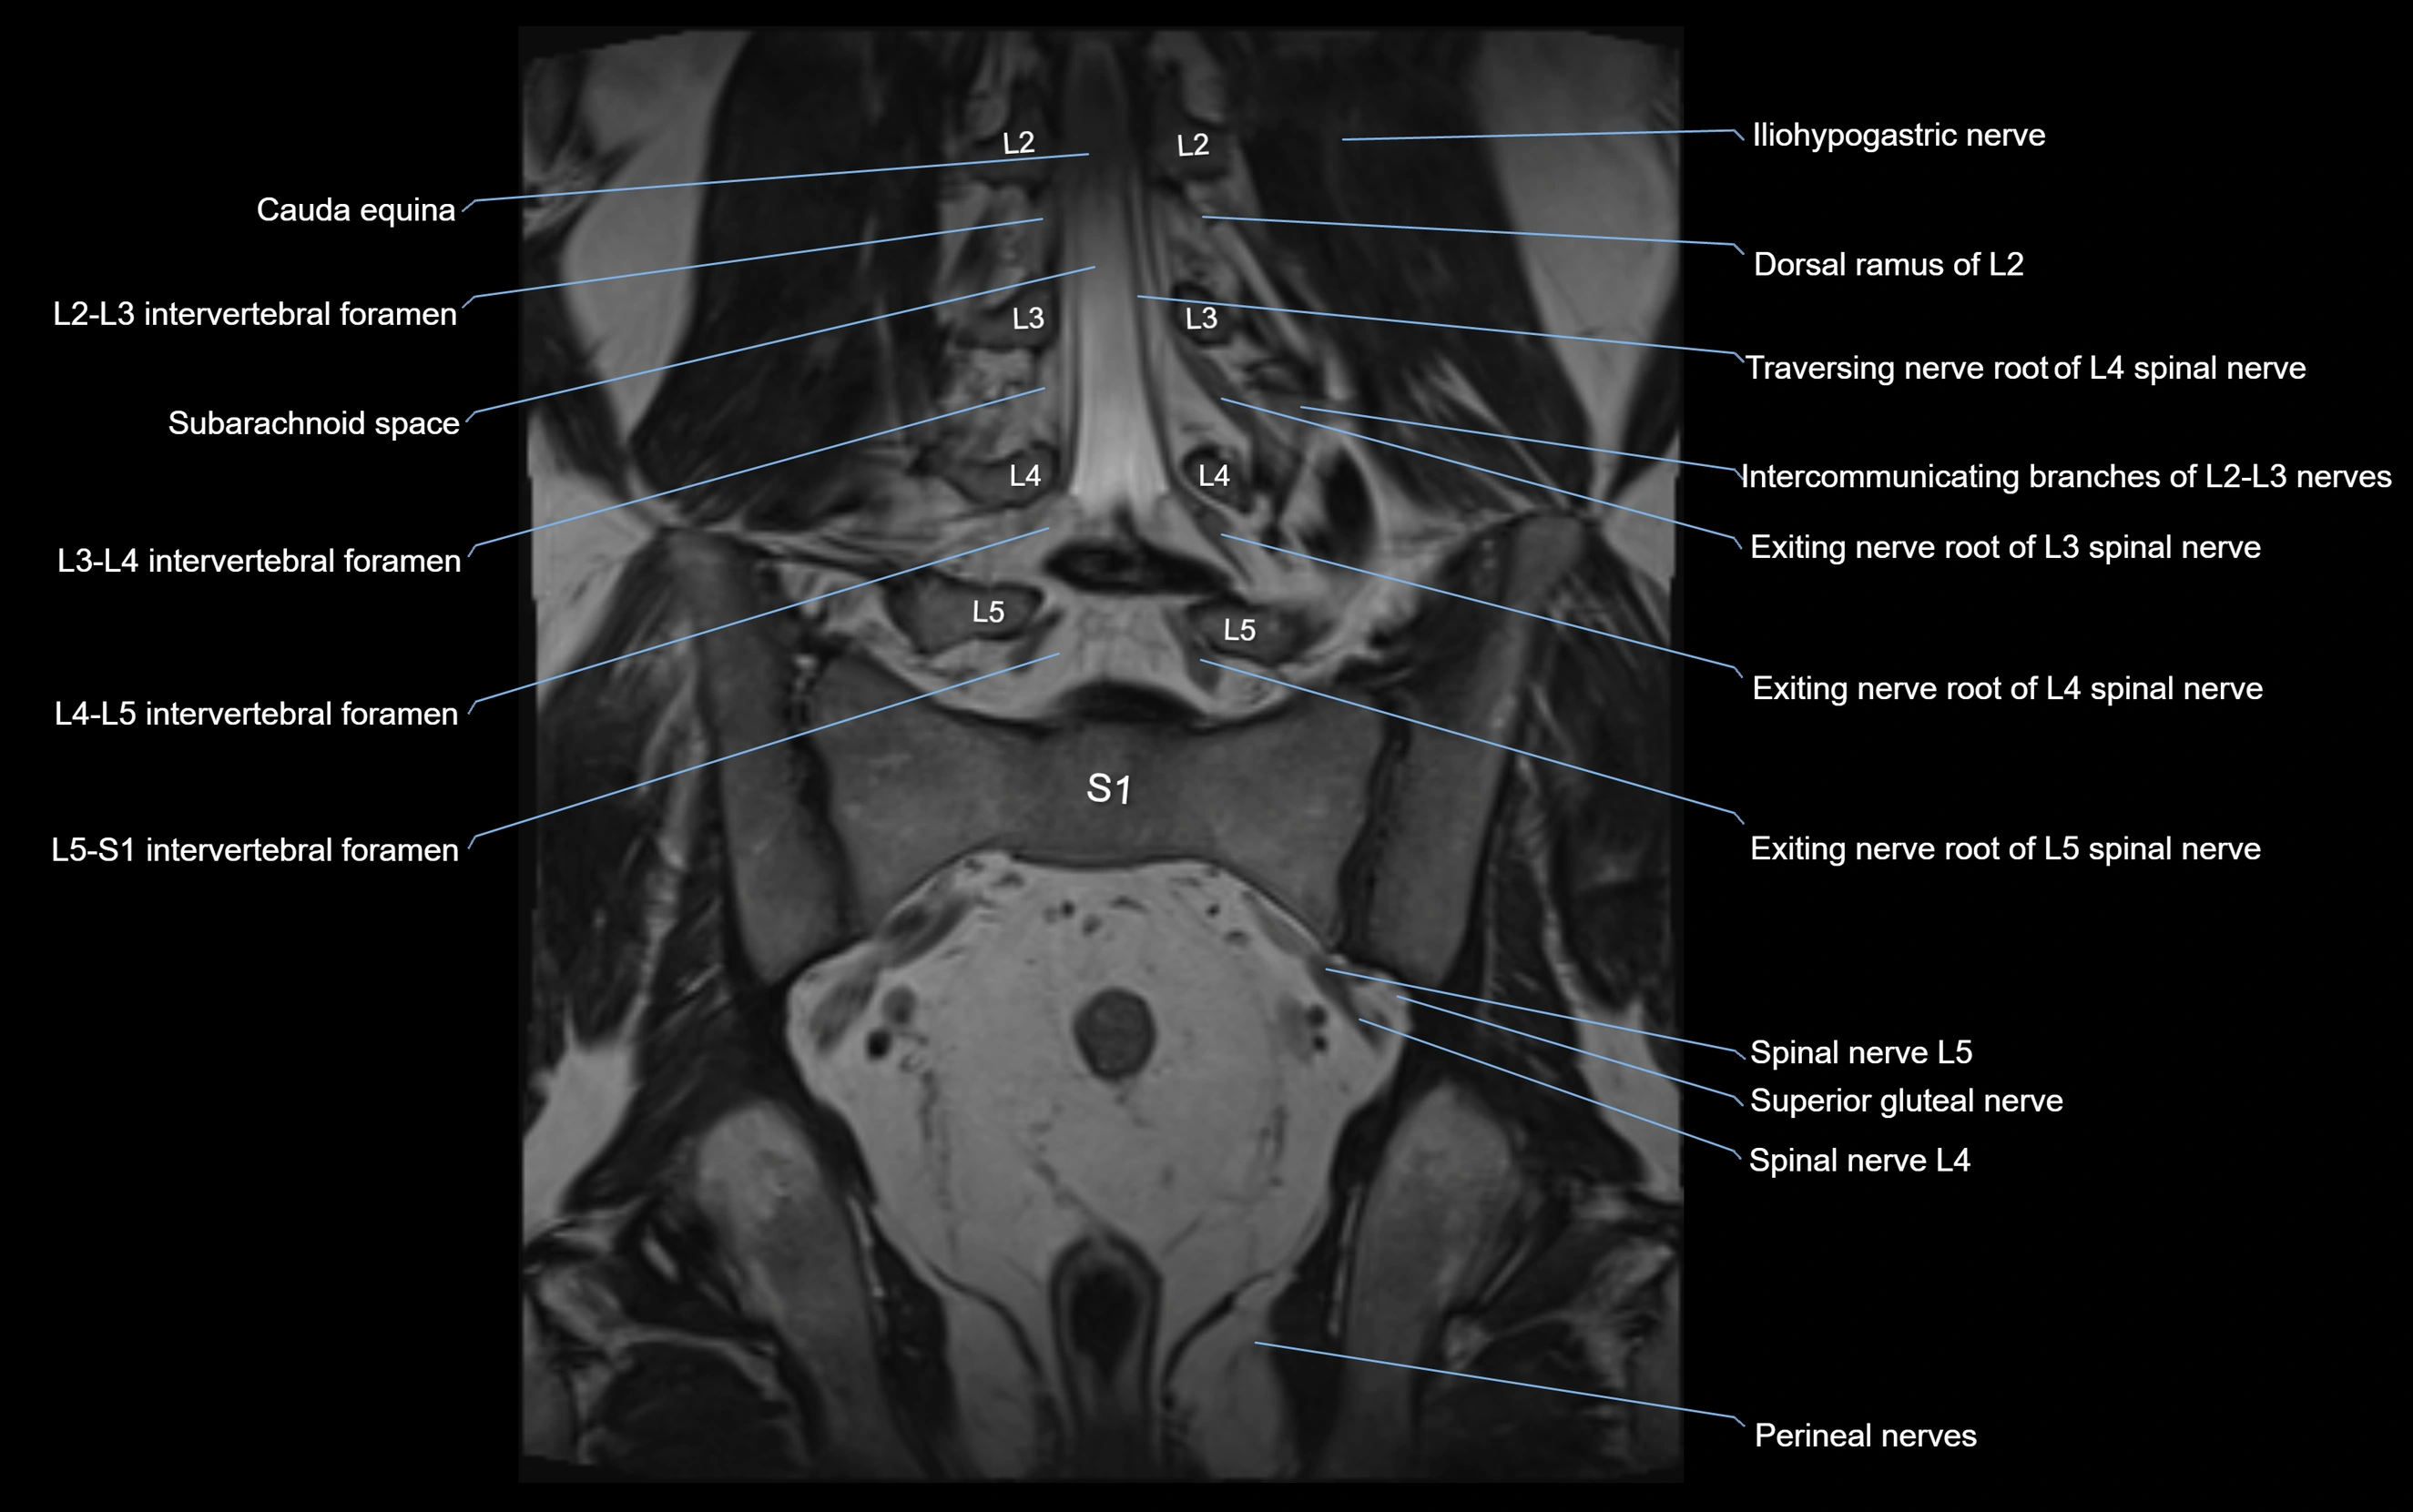

MRI Appearance

T1-weighted images:

• Nerve appears as a very thin low-to-intermediate signal intensity structure

• Surrounded by bright fat, aiding visualization

T2-weighted images:

• Nerve shows intermediate to mildly hyperintense signal compared to muscle

• Pathological involvement appears brighter

STIR (Short Tau Inversion Recovery):

• Normal nerve appears dark

• Inflamed or entrapped nerve appears bright hyperintense

T1 Fat-Sat Post-Contrast:

• Normal nerve enhances minimally

• Pathologic nerve (neuritis, entrapment, tumor infiltration) shows focal or diffuse enhancement

3D T2 SPACE / CISS:

• Nerve appears intermediate to mildly hyperintense compared to muscle

• Surrounded by bright fat or CSF, improving visualization

• Best sequence for mapping small pelvic nerves such as the anococcygeal